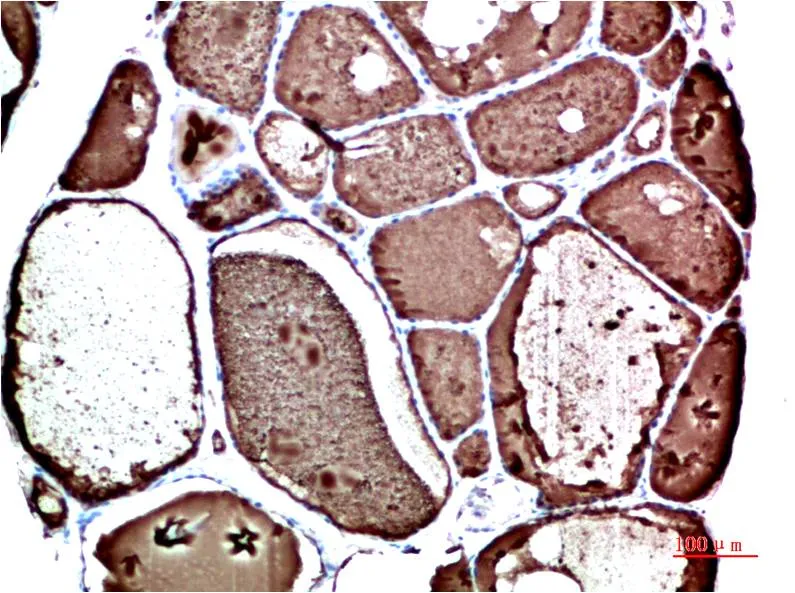

Prealbumin (1F6) Mouse Monoclonal Antibody

Cat: AMM00893

Size1:50μl Price1:$150

Size2:100μl Price2:$280

Size3:500μl Price3:$1200

Size2:100μl Price2:$280

Size3:500μl Price3:$1200